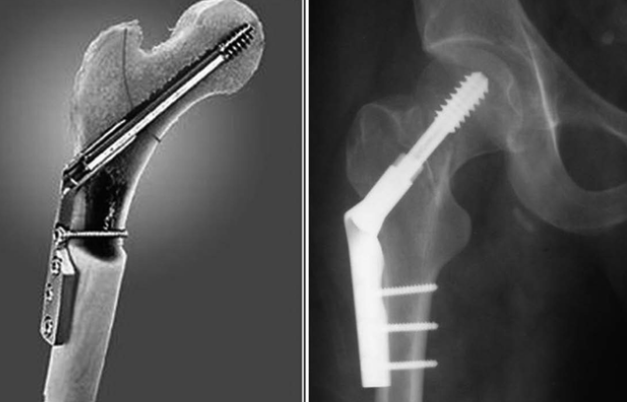

В случае перелома шейки бедра компания МосРентген Центр госпитализирует в Склиф для эндопротезирования.